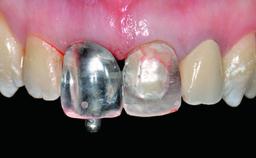

A healthy 28-year-old female patient presented for a consultation on treatment options to restore her upper right central incisor. At the clinical examination, the tooth responded to percussion and palpation. The gingiva was red and slightly swollen, with a mid-facial probing depth of 10 mm. The upper right lateral incisor showed no signs or symptoms, did not respond to exploration and percussion, and the vitality test was positive. The periapical radiograph revealed that tooth 11 had been endodontically treated, with no lesion evident at the apex. A small radiopaque calcified structure surrounded by a narrow radiolucent zone (3 × 3 mm) was present at the apex of tooth 12.